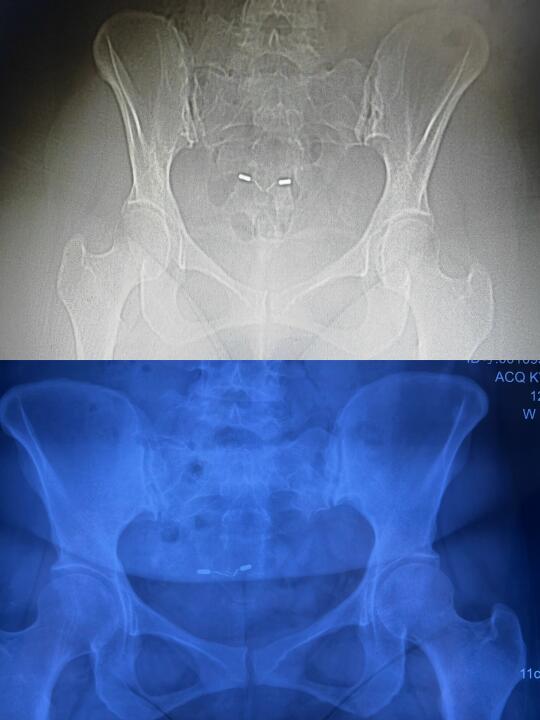

今天案主结束五天的矫正训练 昨天安排她今天上午去拍片子 从片子对比来看骨盆形态发生很大的变化 原来骨盆是长的 两个髂骨原来特别小 也就是左右髂前上棘都是内扣的 并且右边比左边扣得更厉害 现在两个髂骨形态上基本趋近正常 当然左右还有些差异 髂骨从小变大 说明左右髂骨相对于矫正前 向前旋了很多 另外注意看小转子到坐骨外侧的距离 矫正后的片子看明显距离大多了 说明坐骨比原来靠近了 再注意看股骨头顶在髋臼的位置 原来股骨头顶在髋臼偏上 矫正后股骨头顶的位置相对向下了 髂骨相对原来旋前所以她坐着腰就有力了 坐骨靠近后她感觉到坐骨把整个身体顶起来了 并且左右坐骨接近平衡了 能坐正了 原来坐不正 矫正前觉得右边坐骨硌左边没有支撑力 左右差异很大 之前走路腿迈不动要靠上身拽 腰胯腿都没有力 腰部是晃的 矫正后腰胯腿有力 走路腰不晃了而胯可以扭动了 能感觉到股骨头活动比原来丝滑多了 爬楼梯原来腿抬不起来 膝盖不舒服 现在爬楼梯股骨与膝关节都很轻松 能清晰地感觉到股骨头的滑动 人身上感觉少了几十斤 平躺的时候腰部悬空 矫正后腰能自然贴床 睡觉就觉得很放松与踏实 原来腰疼 骨盆周围疼 耻骨周围疼 腹股沟牵扯 尾椎疼 现在随着骨盆的调整身上各种痛症基本解除 还有就是原来中医说她是上热下寒 之前小腹臀部腰都是凉的而且会出凉汗 矫正后感觉骨盆区与腰腹和上半身的温度一样了 也不出凉汗了 因为她的骨盆极度后倾加向下掉 腹股沟挤压得非常厉害 股动脉一定压力大 所以血向下流不畅 骨盆与股骨头的角度变化后 腹股沟的空间打开些 自然股动脉的压力小了自然气血就通畅了 盆腔与下肢的温度自然提高了 其实很多中医诊断为上热下寒的问题的基本上骨盆与股关节都有问题